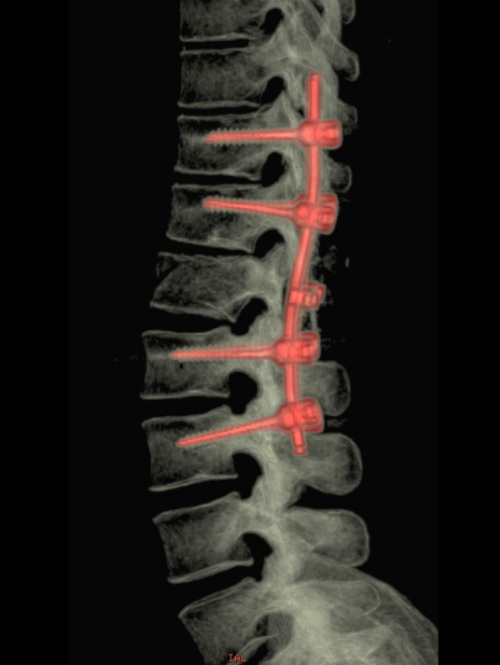

La voie postérieure correspond à la technique classique, qui peut être réalisée facilement en urgence. On peut utiliser chacune de ces procédures individuellement ou en réalisant l’association des différentes techniques permettant d’augmenter la stabilité (Figure 2).

Figure 2 : Association de techniques pour une fracture complexe : Chirurgie par voie antéro-latérale et fixation postérieure percutanée